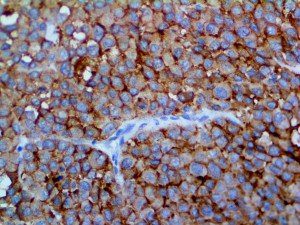

The first cytokines released are interleukin 1β (IL-1β) and tumor necrosis factor-α (TNF-α), which attract a variety of circulating white blood cells (WBCs) to the infection site, including neutrophils, monocytes, macrophages, and natural killer (NK) cells. This response, along with the antipathogenic chemicals released by these cells (i.e., complement), comprise the innate immune response. These cells directly attack the invading pathogen and also release additional cytokines, chief among them interleukin-1 and 6 (IL-6). IL-6 is essential for invoking the adaptive immune response, which calls T-cells, B-cells, and T helper (Th) cells to the infection site. IL-6 also stimulates further recruitment, proliferation and activation of macrophages.

It is the ICU physician who is most likely to witness one of the deadliest manifestations of the abnormal immunological response, the cytokine storm syndrome (CSS). This response is also referred to by some as the cytokine release syndrome (CRS). CSS is characterized by continuous activation and expansion of macrophage and lymphocyte populations, which secrete large amounts of cytokines, causing the cytokine storm. This massive cytokine release is akin to hemophagocytic lymphohistiocytosis (HLH) disease, a syndrome characterized by initial unchecked and persistent activation of cytotoxic T lymphocytes and NK cells.